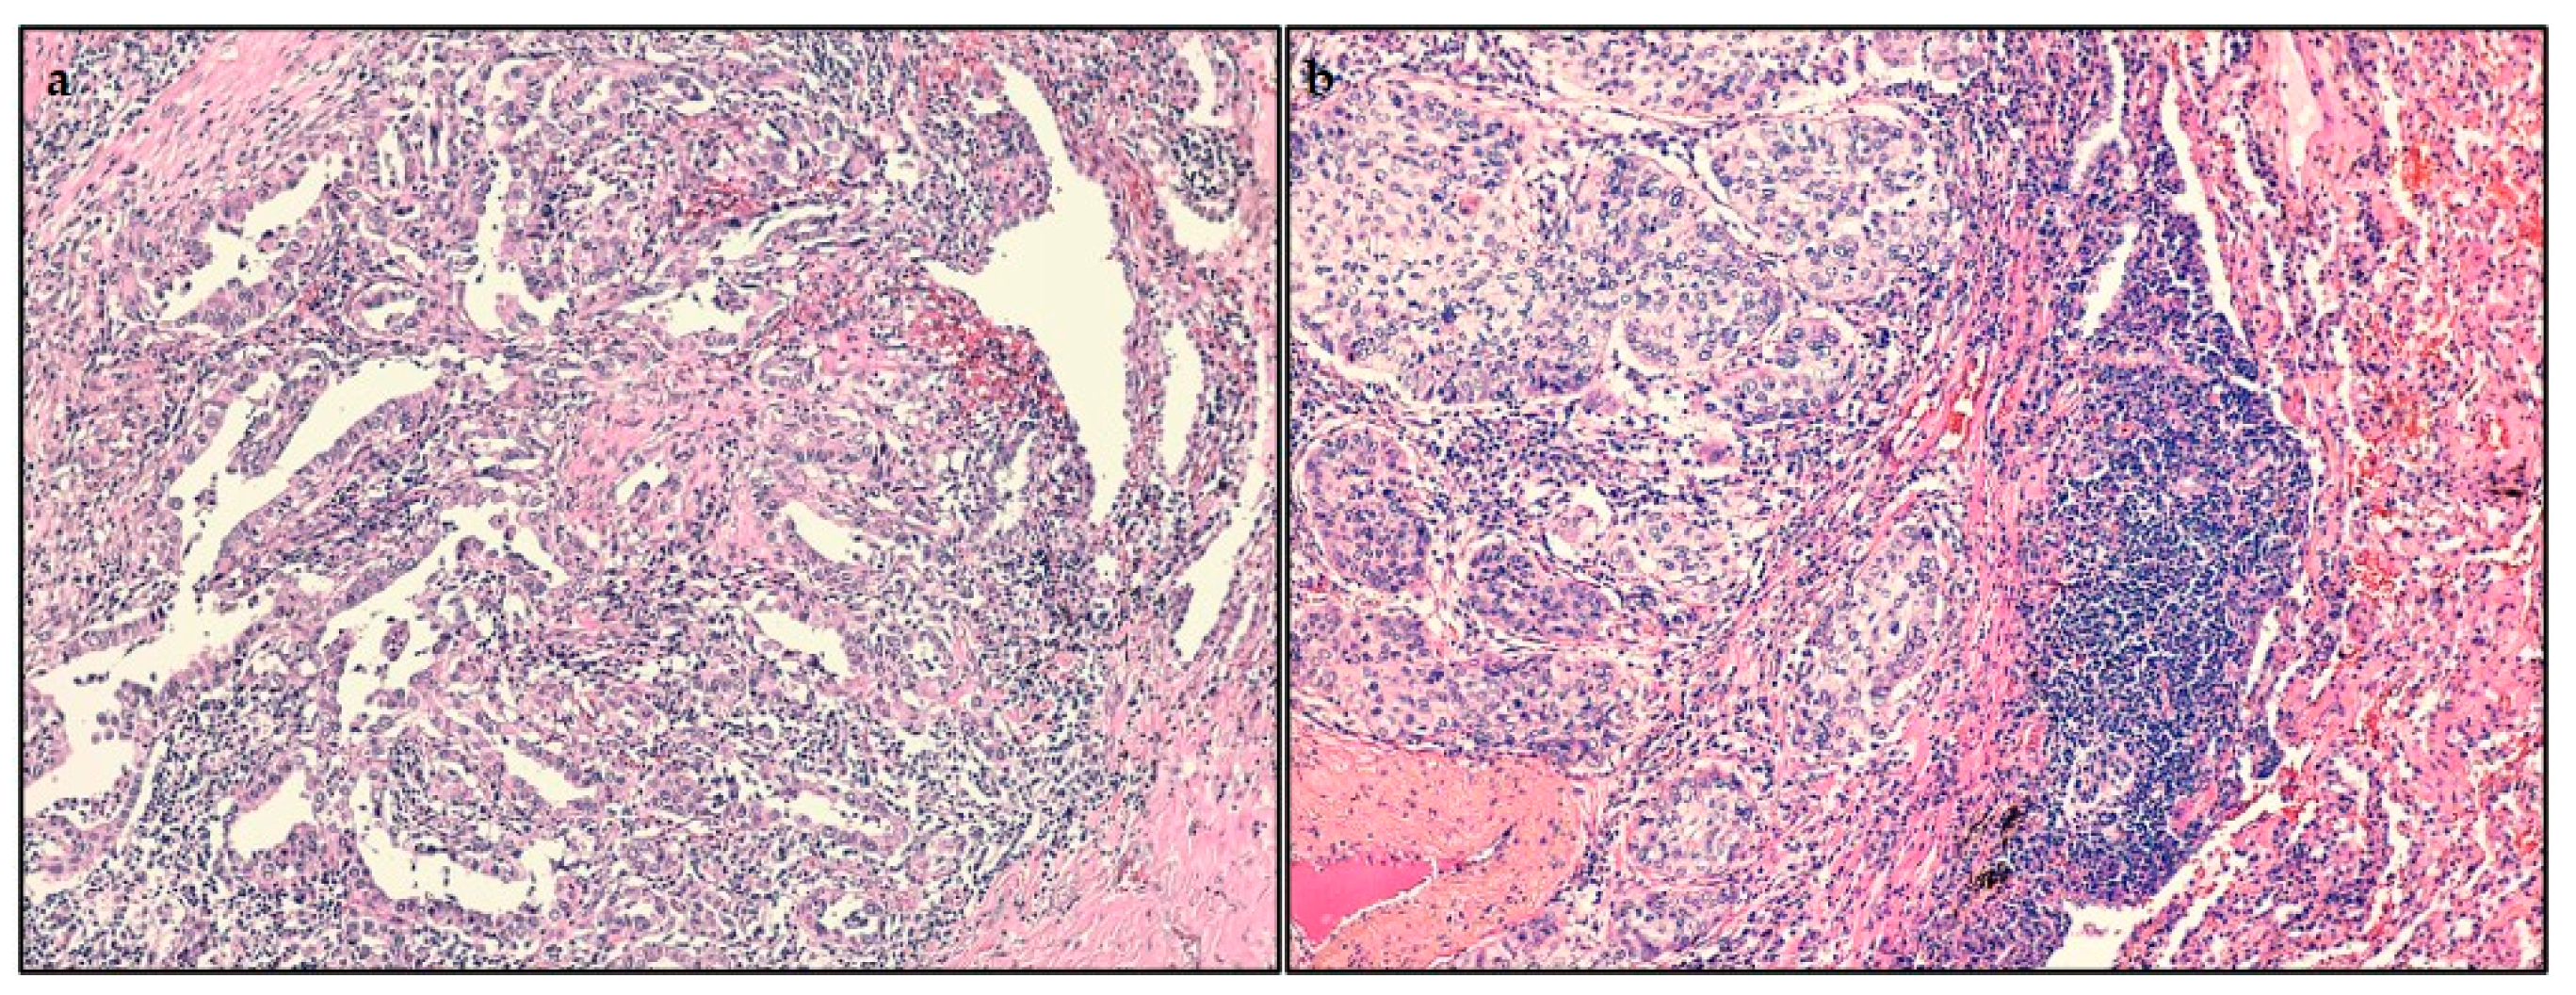

2.2. Histopathological Findings

2.3. Analysis of Tumor-Infiltrating Lymphocytes (TILs)